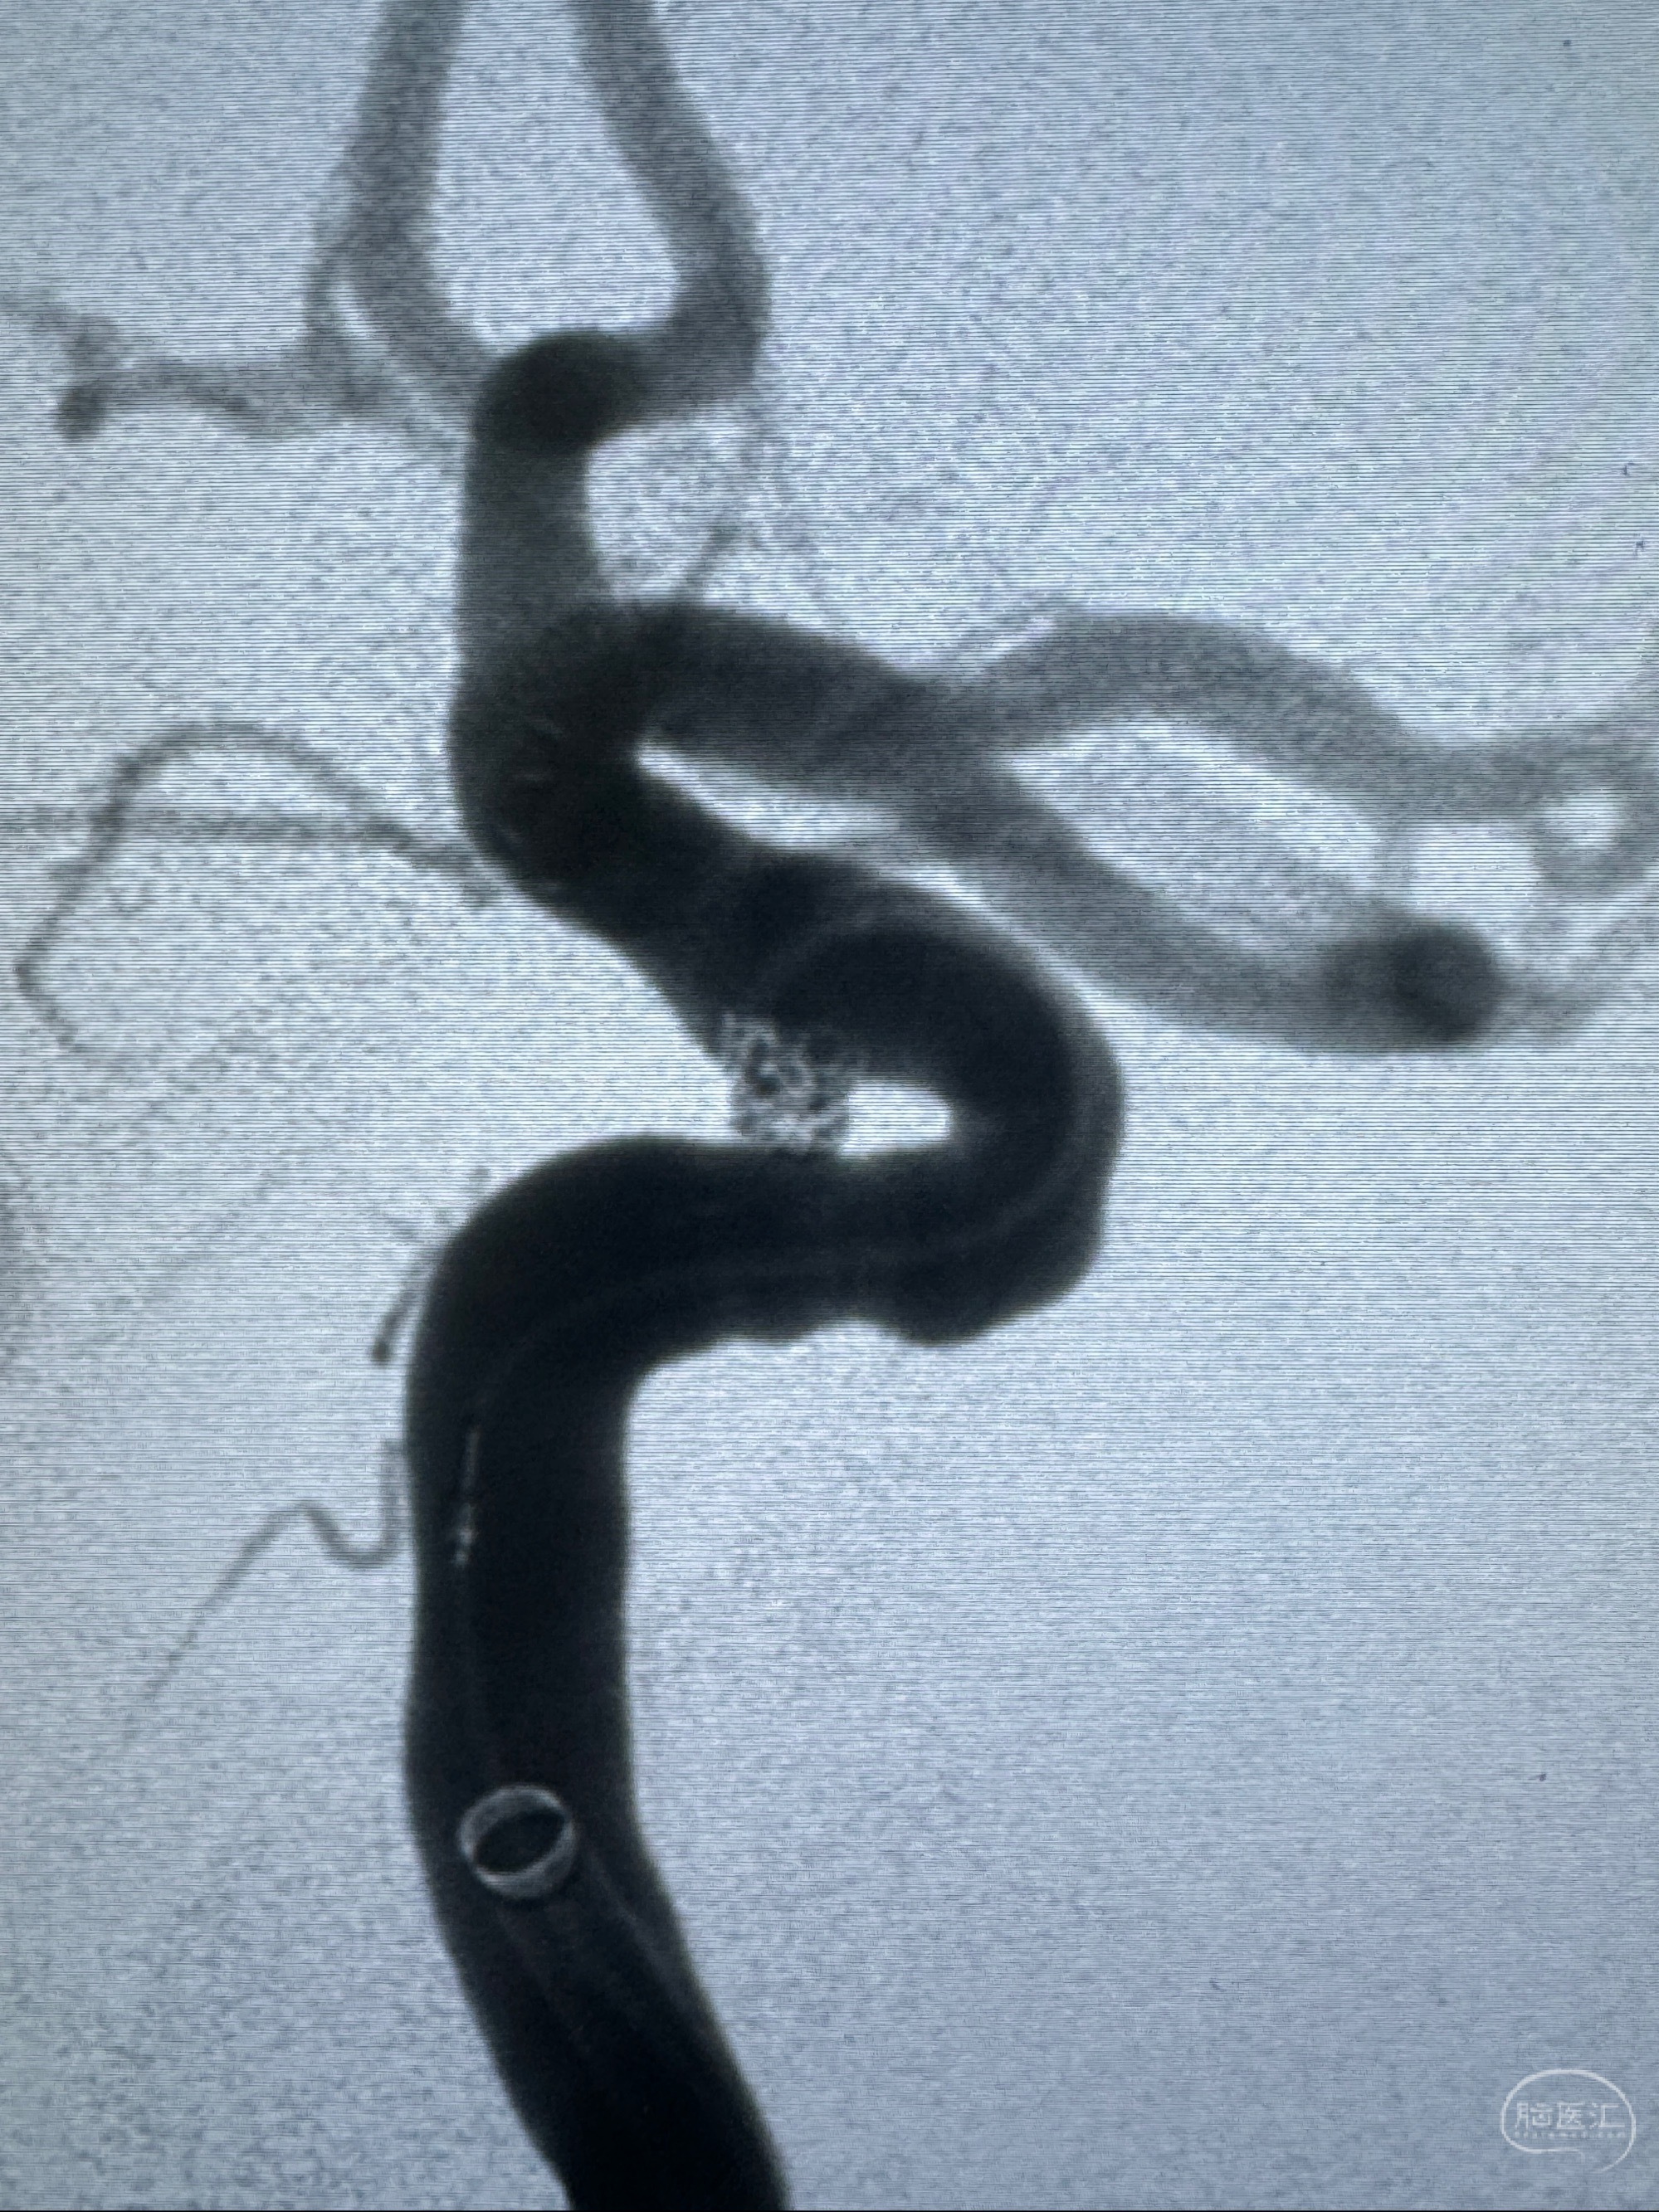

2023-11-03 蓝十字脑科医院 头颅CTA:左侧颈内动脉C6段微小动脉瘤可能(约2mm),右侧大脑前动脉A1段纤细(对侧优势),左侧大脑中动脉提前分叉。

2023-11-13DSA:左侧颈内动脉眼动脉后壁动脉瘤

2023-11-29全麻下行NeuroformEZ4.5-20mm支架辅助栓塞